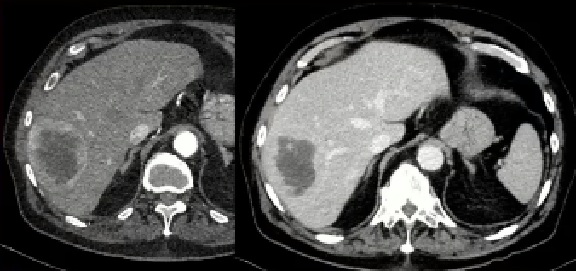

· “放射段切除” (Radiation Segmentectomy):这是LEGACY研究采用的核心技术。它不是对半个肝脏进行大范围照射,而是通过超选择性插管,将微导管精准插入肿瘤的供血动脉分支,只对肿瘤及其周边极窄的边缘(一个肝段)进行超高剂量的放射。

· 消融级别剂量:研究中,肿瘤所接收的中位吸收剂量高达410 Gy。这远超我们之前讨论的100-120 Gy的“有效阈值”,进入了“消融剂量”的范围。这种剂量足以彻底摧毁目标区域内的所有细胞,达到与物理消融(射频、微波)或手术切除相似的效果。